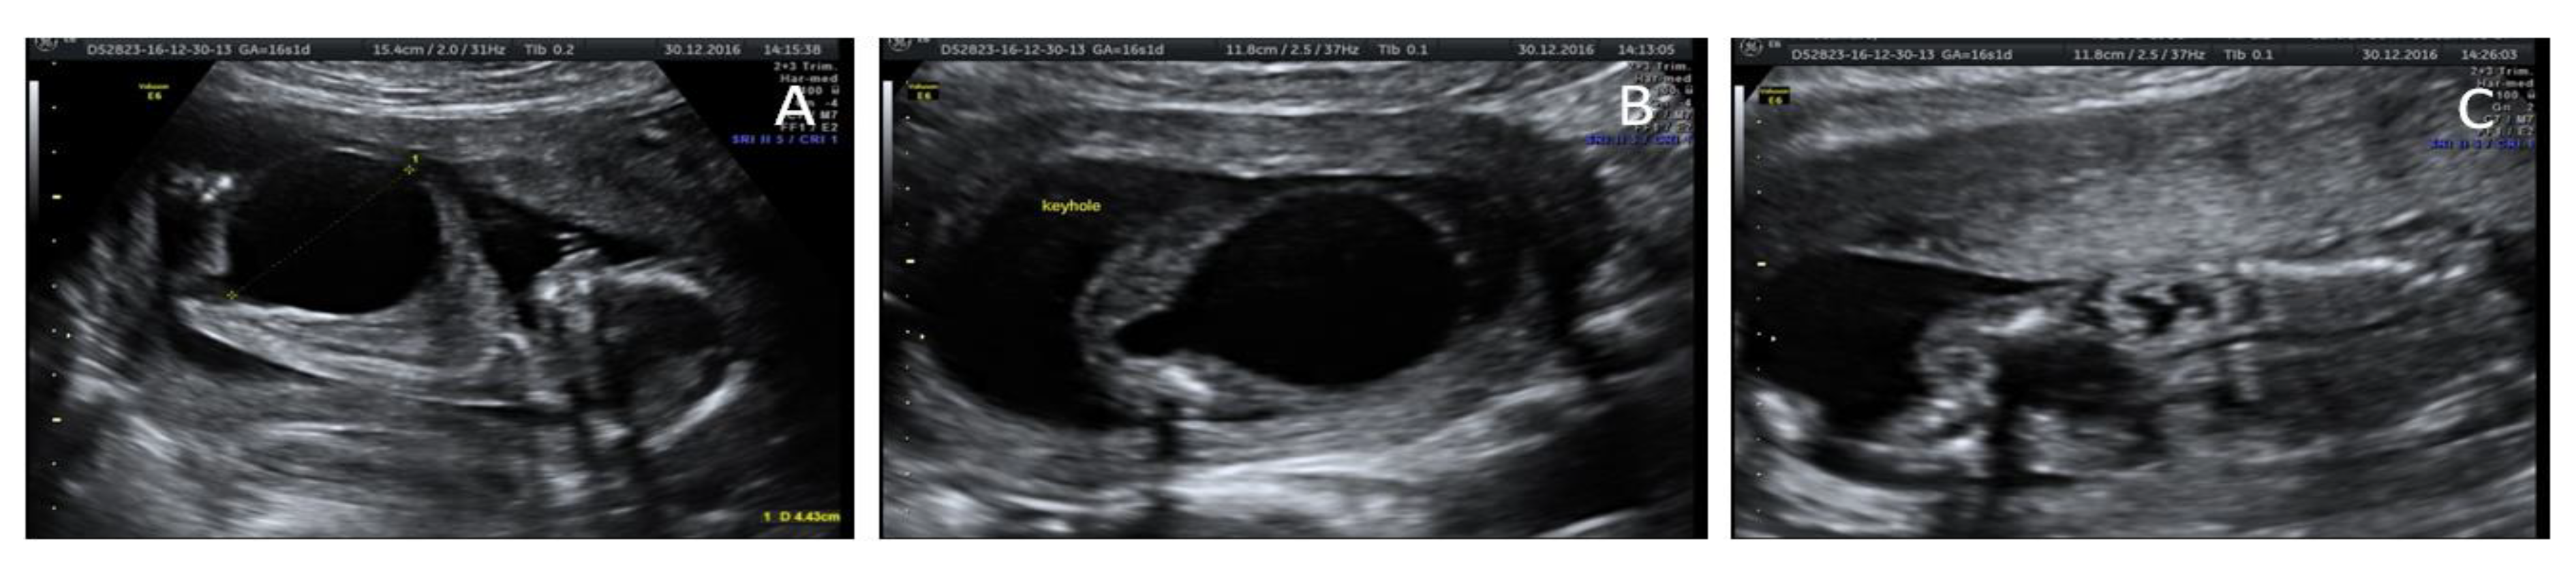

"Keyhole" bladder. Axial view of a distended fetal bladder in an Bladder Keyhole Sign The most common symptom is a urinary tract. In addition, ureteral dilation may be seen because of the. Symptoms of posterior urethral valves can range from moderate to severe. The keyhole sign is an ultrasonographic sign seen in boys with posterior urethral valves. The ‘keyhole sign’, representing a dilatation of the posterior urethra in patients with posterior urethral obstruction 10,. Bladder Keyhole Sign.

Keyhole sign on prenatal ultrasonography. Download Scientific Diagram Bladder Keyhole Sign In addition, ureteral dilation may be seen because of the. The presence of the keyhole sign alone was not found to be predictive of a diagnosis of puv (p = 0.27). The ‘keyhole sign’, representing a dilatation of the posterior urethra in patients with posterior urethral obstruction 10, is thought to be a very specific sign of puv. Symptoms of. Bladder Keyhole Sign.

"Keyhole" bladder. 3D rendering of distended bladder in a 19week Bladder Keyhole Sign The ‘keyhole sign’, representing a dilatation of the posterior urethra in patients with posterior urethral obstruction 10, is thought to be a very specific sign of puv. The keyhole sign is an ultrasonographic sign seen in boys with posterior urethral valves. The presence of the keyhole sign alone was not found to be predictive of a diagnosis of puv (p. Bladder Keyhole Sign.

Ultrasound of fetal bladder with classic "keyhole sign" (8). Download Bladder Keyhole Sign It refers to the appearance of. A keyhole sign detected on ultrasound indicates obstructive uropathy, with posterior urethral valves being the most common cause. The presence of the keyhole sign alone was not found to be predictive of a diagnosis of puv (p = 0.27). The keyhole sign is an ultrasonographic sign seen in boys with posterior urethral valves. The. Bladder Keyhole Sign.

Antenatal ultrasound of fetus demonstrating “keyhole” sign indicative Bladder Keyhole Sign The presence of the keyhole sign alone was not found to be predictive of a diagnosis of puv (p = 0.27). “keyhole” sign, is commonly associated with posterior urethral valves (figure 2). A keyhole sign detected on ultrasound indicates obstructive uropathy, with posterior urethral valves being the most common cause. The ‘keyhole sign’, representing a dilatation of the posterior urethra. Bladder Keyhole Sign.